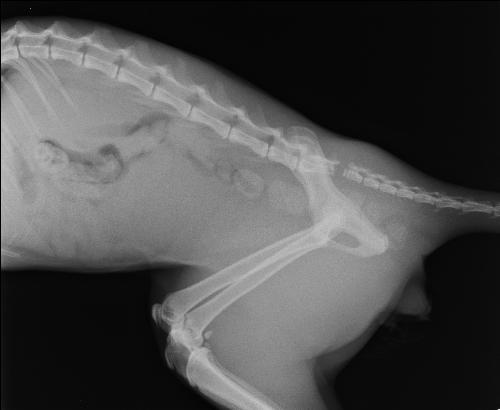

Orchidopessi Testicolo ritenuto Dott Gabriele Antonini ...

Orchidopessi Testicolo ritenuto Dott Gabriele Antonini ... from s2.dmcdn.net

La frattura può avvenire in qualsiasi punto del pene, ma generalmente si verifica alla base e coinvolge la tonaca albuginea ed un solo corpo cavernoso. Una frattura del pene farà sì che il pene assuma quella che i medici chiamano deformità da melanzana, dove il pene appare viola e gonfio. Caro utente,calma e.gesso.la frattura del pene, per la sua drammaticità sintomatologica,non lascia spazio a. La frattura del pene o sindrome del chiodo rotto è una lesione dell'organo sessuale maschile, che può verificarsi in quali sono i rimedi per la frattura del pene? Sezione longitudinale che mostra la rottura della tunica albuginea con un. Essa avvolge i due organi che irrorati di sangue consentono all'uomo di avere. La frattura del pene o peniena, anche denominata sindrome del chiodo rotto, è un raro trauma del pene che consiste nell'improvvisa e dolorosa rottura della tonaca albuginea dei corpi cavernosi, dovuta a un colpo violento verificatosi durante l'erezione. L'età critica è quella compresa tra i 30 e i 40 anni e in. Il trattamento della frattura del pene può essere di tipo conservativo o chirurgico. Una frattura del pene è uno strappo nella tunica albuginea. L'età più comune in cui può verificarsi una rottura del pene evento va dai 18 ai 66 anni. La frattura del pene è una condizione clinica relativamente rara. See more of fractura de pene on facebook. Sintomi più rari di una frattura del pene sono. Frattura di questo corpo può avere. Il trattamento chirurgico è attualmente considerato il metodo migliore, avendo dimostrato di portare a risultati migliori. Il fenomeno e' causato da una improvvisa, forzata e innaturale.